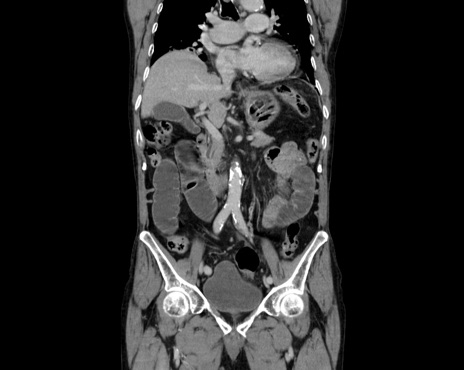

症例26(冠状断像)

【症例】80歳代男性

【主訴】嘔吐

【現病歴】昨晩2回嘔吐あり、今朝になっても嘔吐あり。来院。

【既往歴】胃潰瘍

【身体所見】意識清明、BT 37.6℃、BP 166/95mmHg、HR 100bpm、SpO2 97%、腹部:平坦・軟、腸蠕動音聴取良好、圧痛なし。

【データ】WBC 21900、CRP 1.4